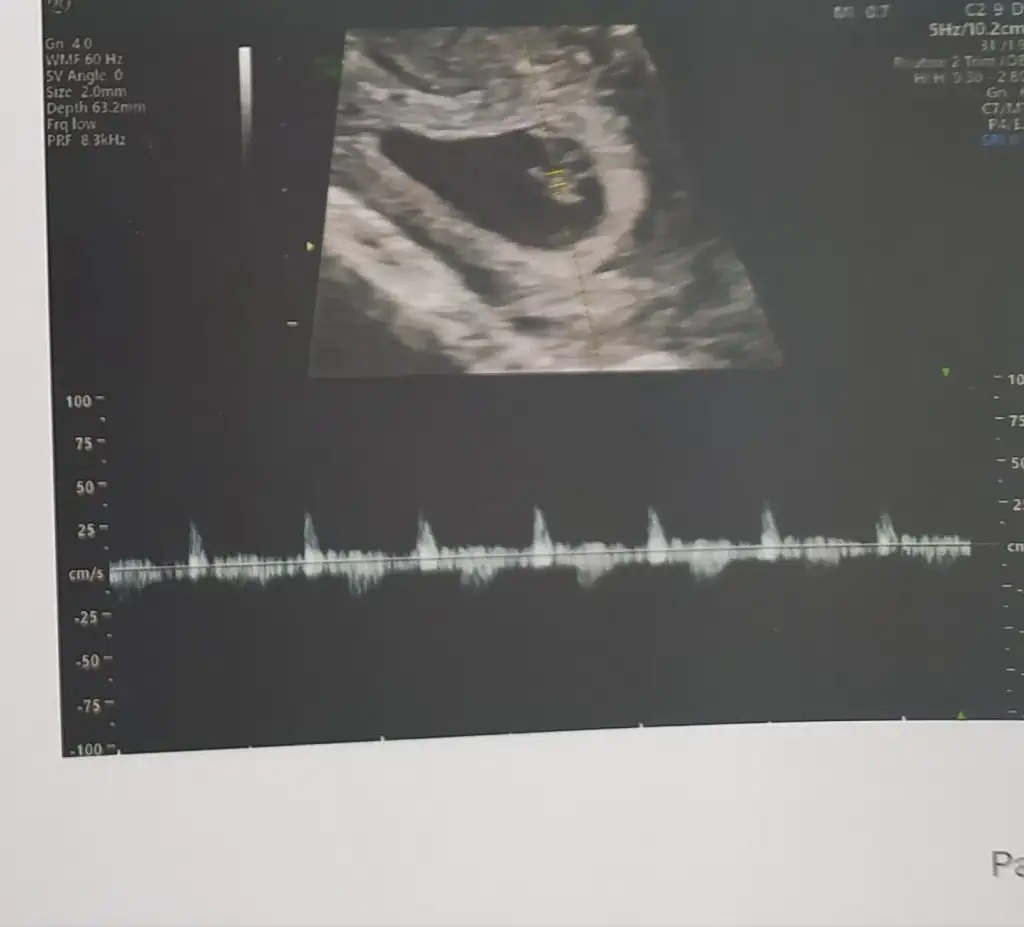

paşa mı sankiMerhaba 6+4 vajinal ultrason görüntüsüne yorum yaparmısınız çok merak ediyorummEki Görüntüle 3069814

Canım benim fotoğrafımı da yorumlar mısın 7 hafta karındanben kız olarak yorumladım ama bu de sen bak

Ben de merak ediyorum:) karından 6 haftalıkSelam Kızlarbir çok kişi gruplardan beni bilir. Yine yetiştim imdatlara

Geç oldu ama 7+1 buna da bakar mısınız

Evet karından bakildikarından mı bakıldı?